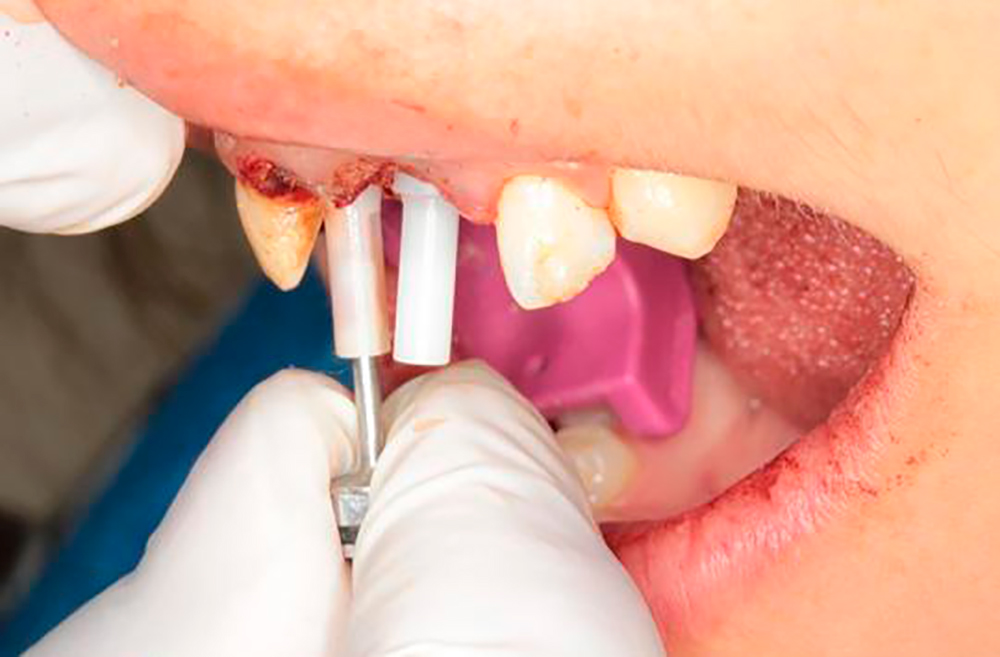

Socket preparation prior implant placement Using DSI DNT Drills

Premium Spiral Implants placement